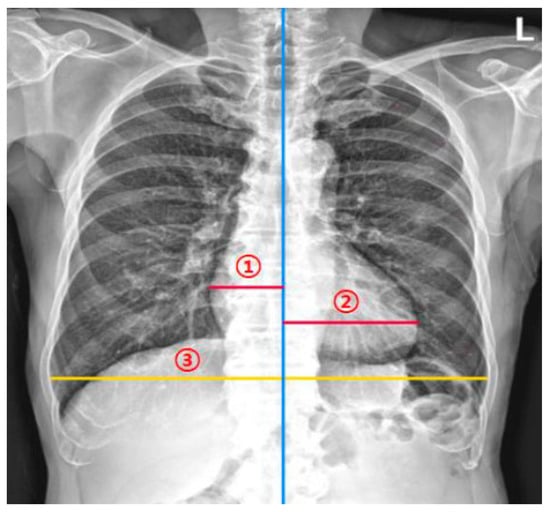

2.1. DL-Based Model Measuring the CTR on Chest Radiographs